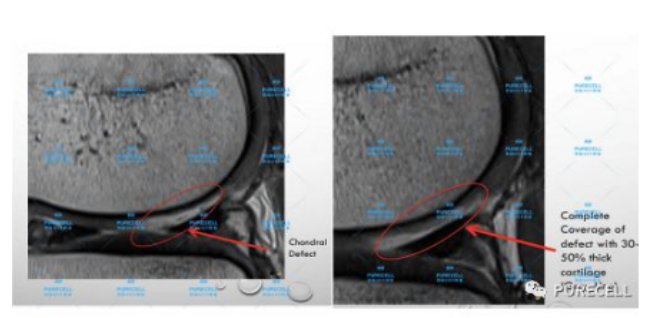

PURECELL首席科學家以及運動醫療專家已經驗證了UCF對膝關節修復的有效性,上圖是UCF軟骨及半月板修復前後影像對比